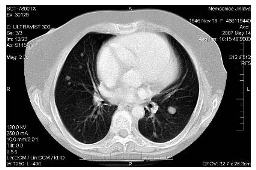

Pac. J. C., ročník 1946. V anamnéze Ebsteinova

anomálie plícnice, jinak bez komorbidit. V březnu 2006 léčena pro

epidermoidní karcinom děložního čípku pT1b pN0 M0 operací podle

Wertheima. V dubnu 2007 zjištěna lokální recidiva (obr. 1) a navíc

mnohočetné metastázy do plic (obr. 2).

Obr.1

Obr.2